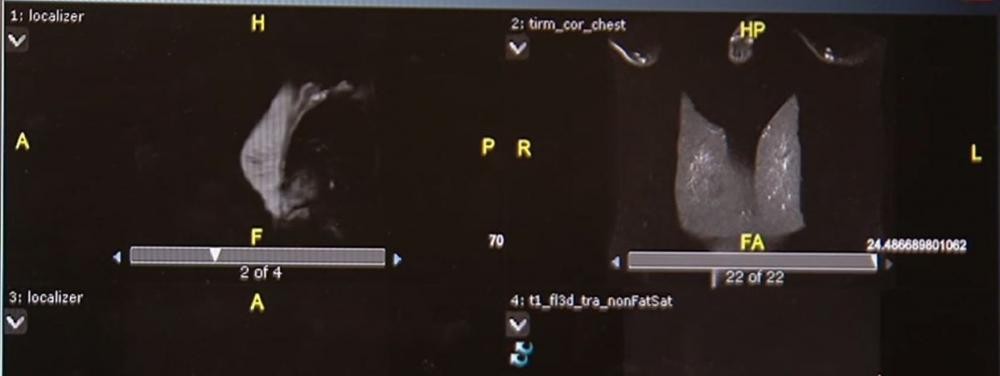

فوفق الباحثين في معهد لقاح السرطان الأميركي التابع لجامعة واشنطن الطبية، أثبتت الدراسة غير العشوائية التي اعتمدت على تجارب سريرية لستٍ وستين مريضة تتراوح أعمارهن بين الرابعة والثلاثين والسابعة والسبعين، ممّن أصبن بسرطان الثدي الإيجابي المسمى علميا بـHER2، أن جرعات لقاح الحمض النووي التي خضعن لها كل ثلاثة أشهر، وفرت مناعة قوية تجاه الورم الرئيسي ومنعته من الانتشار.

الدراسة التي راقبت بيانات المريضات خلال أعوام وجدت أن المريضات اللواتي تم إعطاؤهنّ جرعاتٍ عالية من هذا اللقاح، تحسنت أيضا مناعتهنّ بشكل قوي مع انكماش قدرة البروتين المسبب لسرطان الثدي الإيجابي.